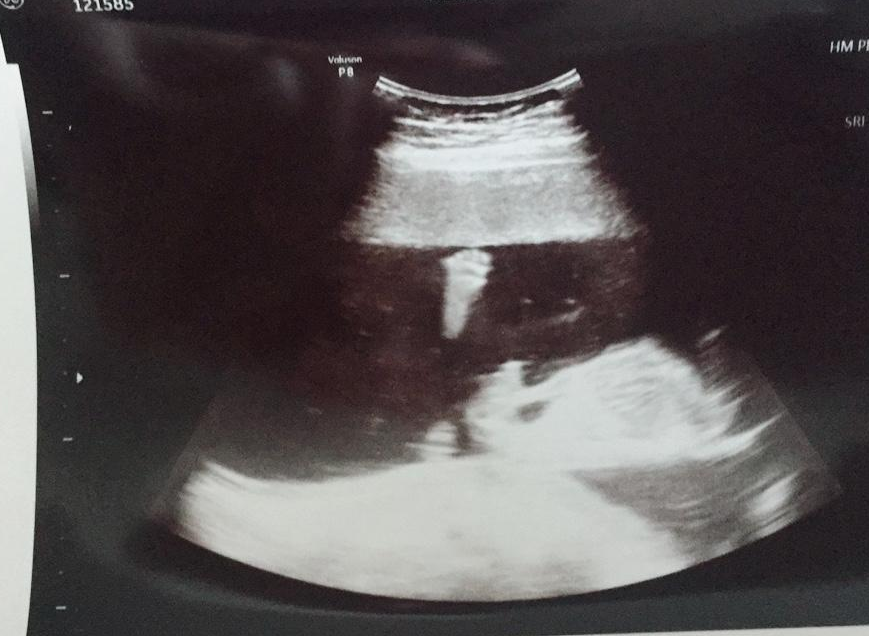

지금 보면 12주때부터 포도(왼쪽)보다 망고(오른쪽)의 양수가 눈에 띄게 많다. 망고는 양수가 많아서 둥둥 떠 돌아다니는 바람에 심장 소리 듣기도 힘들었다. 전조 증상 (개인적 의견)